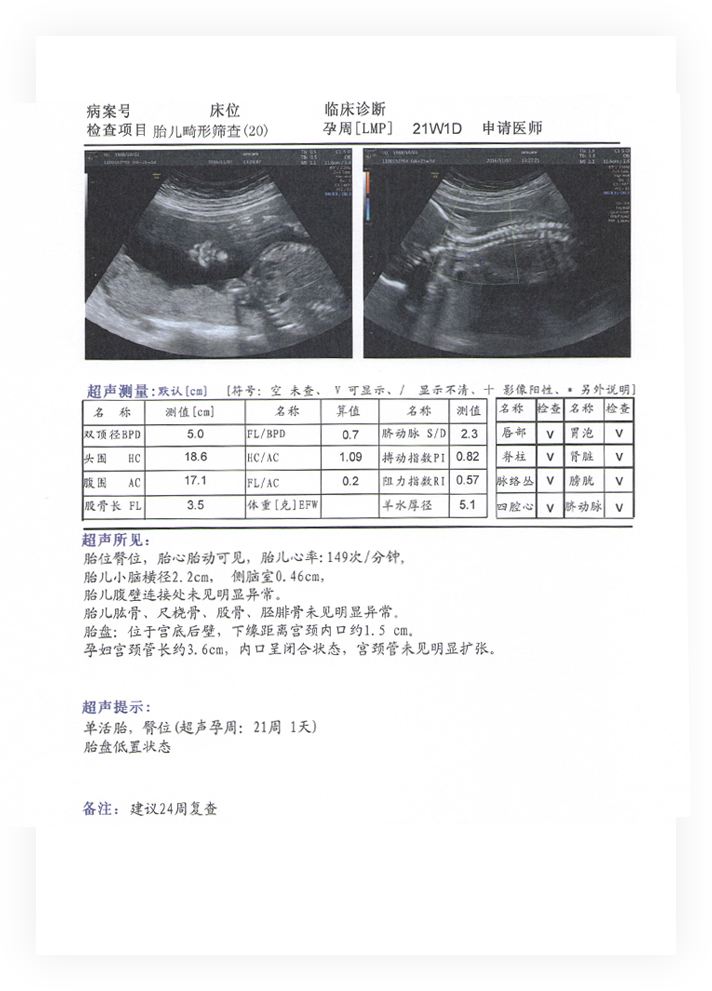

20-24周超聲篩查(畸形篩查)

1、原則

孕20-24周是產前畸形篩查的最佳孕周。

2、目的

依據國家產前超聲篩查的相關規定,在此孕周對嚴重的致命性胎兒畸形進行篩查(包括無腦兒、嚴重腦癱、脊膜膨出、嚴重開放性脊柱裂、胸腹壁缺損內臟外翻、單腔心、致命性軟骨發育不全等)。

3、具體檢查范圍

測量胎兒雙頂徑(BPD)、頭圍(HC)、腹圍(AC)、股骨(FL)、小腦橫徑(Cereb),側腦室后角寬度(lv)。

檢查胎兒顱腦(例:顱骨光環、腦中線、透明隔腔、雙側側腦室、小腦、后顱窩池、大腦中動脈環等)顏面部(例:眼眶、鼻骨、上唇連續性,外耳廓等)脊柱(例:矢狀面、冠狀面等)、心臟(例:四腔心、左、右室流出道、三血管、三血管氣管、主動脈弓、動脈導管弓、上、下腔靜脈等)、胸、腹部臟器(例:心臟位置、雙肺、肝臟、膽囊、胃泡、雙腎、膀胱、臍帶腹壁連接等)、四肢長骨、臍帶數目、臍帶胎盤入口位置、臍動脈血流頻譜S/D值、胎盤位置、羊水、孕婦宮頸長度及內口形態、孕婦雙附件區情況等。